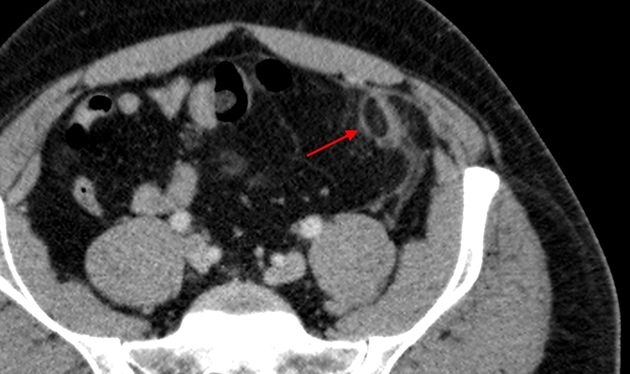

Paciente em tratamento de câncer de bexiga .HD?

A

Colite actínica.

Pode ocorrer durante ou após poucas semanas de exposição à radiação. Quadro clínico: diarreia auto-limitada. Diagnóstico é clínico)

TC (achados inespecíficos):

* Espessamento parietal inespecífico;

* Densificação da gordura adjacente;

How well did you know this?